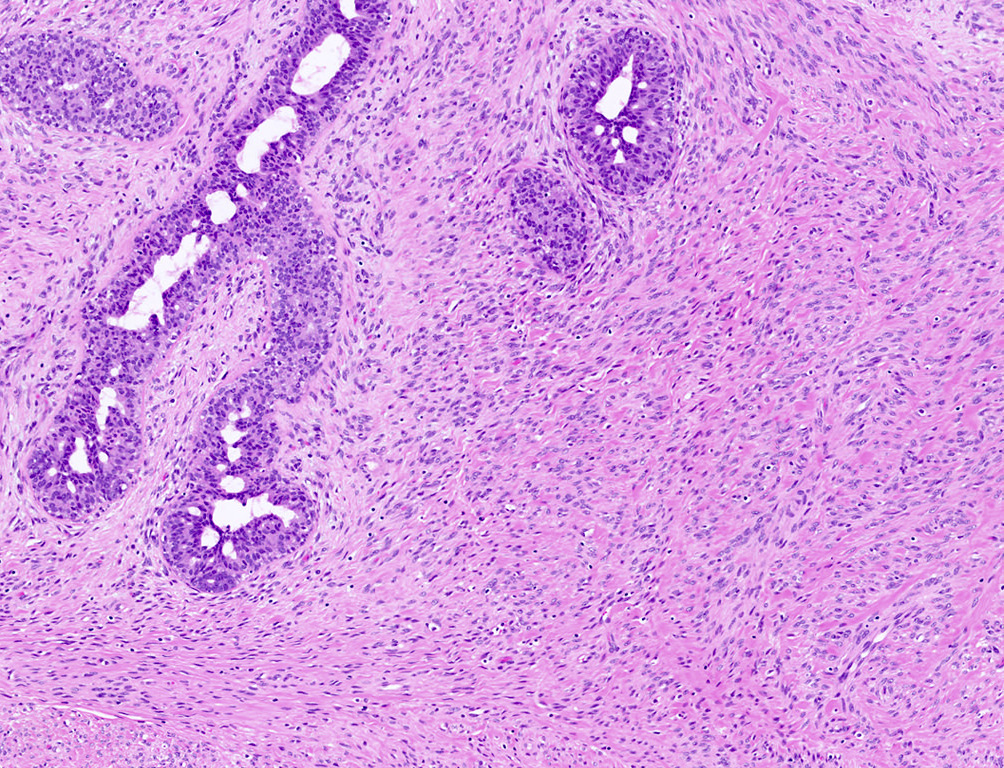

Microscopic (histologic) description

- Well circumscribed, unencapsulated

- Biphasic tumor, proliferation of both glandular and stromal elements

- Glandular component

- Intracanalicular: glands are compressed into linear branching structures by proliferating stroma

- Pericanalicular: glands retain open lumens but are separated by expanded stroma

- Glandular elements have intact myoepithelial cell layer

- Stromal component

- Generally uniform cellularity within a given lesion

- Collagen and bland spindle shaped stromal cells with ovoid or elongated nuclei

- No stromal atypia

- Stroma may show myxoid change or hyalinization

Microscopic (histologic) images

Contributed by Gary Tozbikian, M.D., Debra Zynger, M.D., Azadeh Khayyat, M.D. and Julie M. Jorns, M.D. (Case #533)